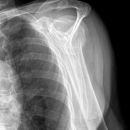

Subcapitale Fraktur und Tuberculum majus